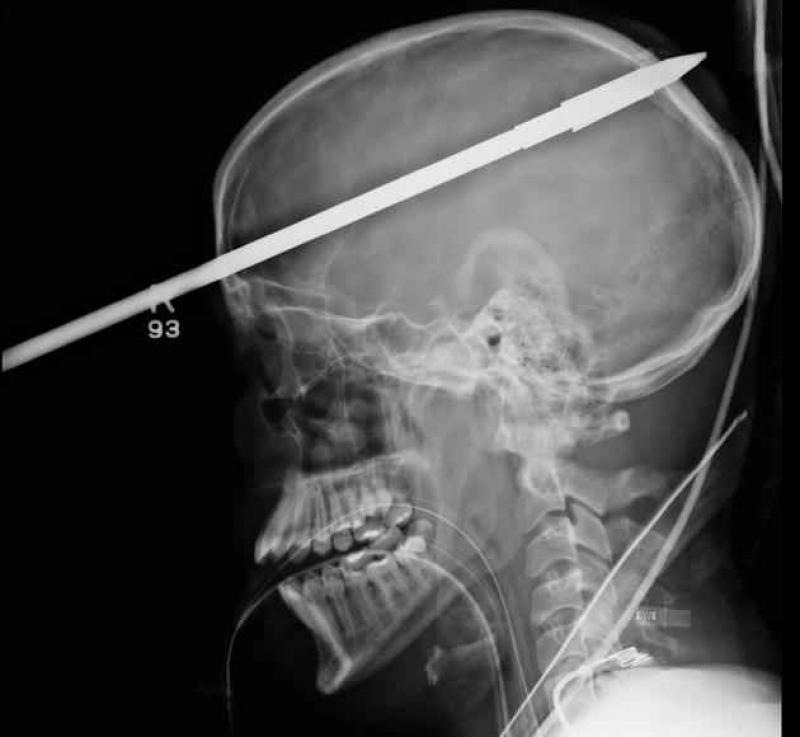

Röntgenfoto's zijn een medische uitvinding die ons al decennia lang helpt. Ze geven een nieuw gezichtspunt als het gaat om het vinden en behandelen van inwendige verwondingen. De machines kunnen opmerkelijke beelden vastleggen van het menselijk lichaam en ze documenteren vaak gruwelijke verwondingen. Een wonde van iemand zien, is al erg, maar als je ook kan zien wat de schade in het lichaam is, dat is nog veel erger. We hebben 12 tegelijk fascinerende, gruwelijke en hilarische röntgenfoto's op een rijtje gezet. Stel jezelf maar eens de vraag hoe iemand ooit aan die verwondingen is gekomen. We beginnen nog rustig.